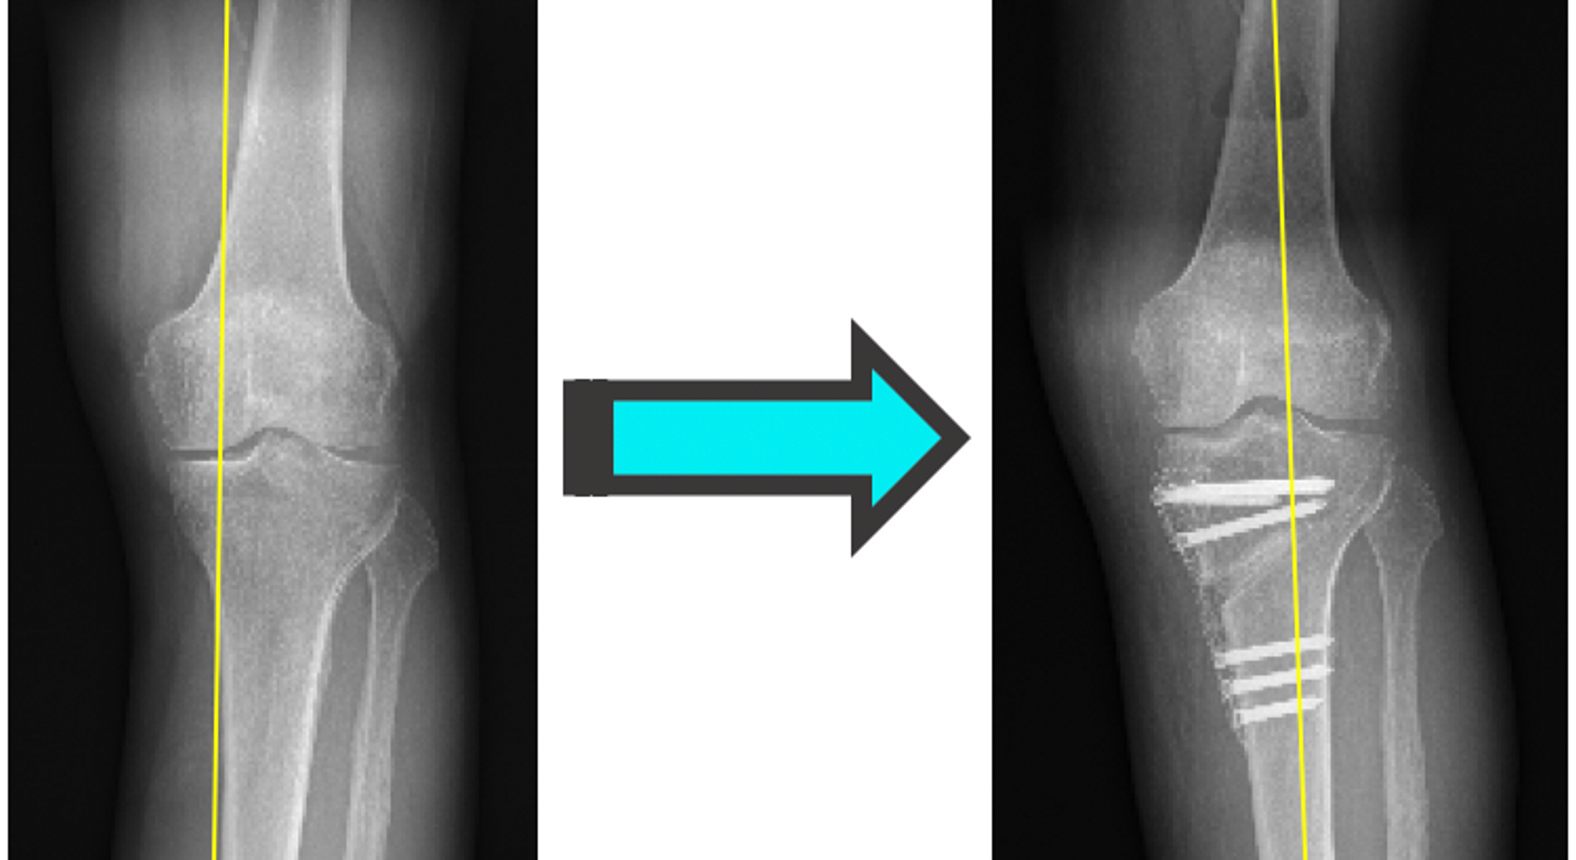

Umstellungsosteotomie Knie Erfahrungsberichte. Positiver Erfahrungsbericht Unterkiefervorverlagerung Umstellungsosteotomie KieferOP 3 Jahren unter massiven Schmerzen und habe Probleme mit den Knien, rechts mehr als links. Rechts fehlt der Innenmeniskus und das Knie zeigt eine Achsverschiebung von 4 Grad

Eintrag von am 17.03.2018 - Anzahl gelesen : 76 Einschränkungen nach Metallentfernung 0 vor knapp 3 Jahren wurde bei mir eine Umstellungsosteotomie am linken Knie durchgeführt Ich mache mir jetzt große Sorgen, weil ich sehr wenige Fortschritte mache mit den Krücken

Knee Realignment Osteotomies Dr A. Theodorides Knee Surgeon. Eintrag von am 04.10.2020 - Anzahl gelesen : 1 Sehr kurzer Erfahrungsbericht Umstellungsosteotomie 0, Ich bin 43 Jahre alt, habe Gonarthrose in beiden Knieen, angeblich Grad 2 (-3) Nun hat er mir empfohlen eine Umstellungsosteotomie zu machen da wird ein Knochenkeil raus gesägt und an einer anderen Stelle eingesetzt einschließlich Platten, damit die Achse dann wieder grade ist.